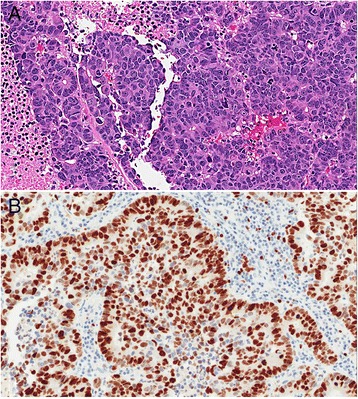

Figure 3.

Large cell neuroendocrine carcinoma. A.H&E, 20x magnification, large cell neuroendocrine tumor with solid and pseudoglandular growth patterns. Prominent nucleoli, geographic necrosis, and mitoses are readily evident. B. Ki-67, 20x magnification, showing 91.9% tumor positivity by digital image analysis.